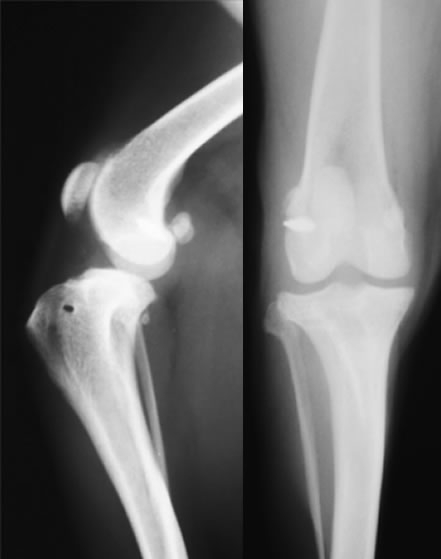

膝蓋骨脱臼グレード2〜3とは

膝蓋骨が大腿骨遠位にある滑車溝から内方もしくは外方に脱臼する疾患です。膝蓋骨外方脱臼の症例では、内方脱臼よりも強い症状を呈することが多いです。

グレード2とは、膝蓋骨を指で押すと簡単に脱臼しますが、指を離しても自然には元に戻らない状態です。日常生活の中で自然に脱臼することがあり、元に戻ると跛行がおさまります。

グレード3とは、普段から膝蓋骨が脱臼したままで、指で押すと正常な位置に戻りますが、指を離すと脱臼した位置にもどる状態です。

若い時期にみられた場合は放置しておくとグレード4にいたる可能性があること、何らかの症状があり日常生活の中で脱臼している場合は膝蓋骨内側の軟骨がすり減り、痛みが強くなるなどの理由から手術による整復を必要とします。

外科手術。おもに、Block Resectionという関節軟骨を温存したまま膝蓋骨がおさまっている溝を深くする方法と、脛骨粗面転移術といい内側に変位している膝蓋靭帯の付着部である脛骨粗面の位置を正しい位置にもどす方法とを組み合わせて行います。